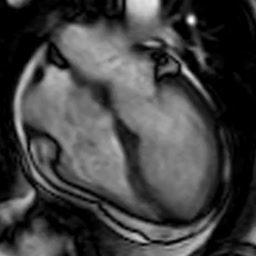

Apical Ballooning